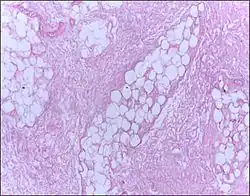

| Micrograph of breast tissue showing fat necrosis. H&E stain | |